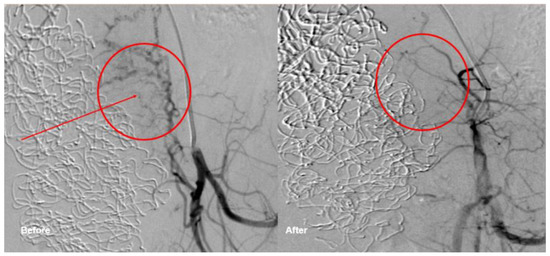

In the following, we present the case of an uncomplicated pregnancy after TAE. This 23-year-old primiparous woman with no pertinent medical history was admitted to a non-tertiary hospital at 40 weeks of gestation for rupture of membranes and beginning labor. In the second stage of labor, fetal bradycardia led to vacuum extraction of a healthy male newborn. Oxytocin (5 IU) was administered intravenously as a bolus; the placenta expulsion occurred ten minutes after delivery. Due to vaginal bleeding despite adequate uterine tonus, 1000 mcg misoprostol was administered rectally, after suturing the episiotomy. 90 min after delivery severe bleeding occurred. The placenta was considered inconspicuous after clinical re-evaluation. Intravenous volume substitution was performed, and ephedrine was administered for circulatory instability, a continuous perfusion of sulprostone was started before confirming the need for surgical revision. The blood loss was estimated at 3500 mL at this point, hemoglobin level was 69 g/L. Consequently, four RBCUs and two units of fresh frozen plasma (FFP) were administered. Curettage was performed but complicated by massive bleeding. Therefore, the patient was transferred to our primary care center. Due to the persistent bleeding and uterine atony, a repeat surgical revision was performed. The cervix showed a small tear, without significant bleeding. Blood clots and placenta-like tissue were evacuated from the uterine cavity. (Eventually, the histopathology revealed only decidua and blood, but no placental tissue.) Bakri®-Balloon placement was unsuccessful, and four sulprostone soaked compresses were inserted into the uterine cavity. The patient was stabilized by administration of a further seven RBCUs, eight units of FFP, three units of platelet concentrates (PLT), 2 g tranexamic acid (TXA), 4 g fibrinogen, and activated recombinant human factor seven (rhFVIIIa): However, as the bleeding control was not yet satisfactory, TAE was performed by our interventional radiologists (Figure 2) in order to avoid laparotomy as well as hysterectomy. The right uterine artery and parametran branches of the left uterine artery were embolized with Gelfoam®. Post-surgery, the patient was taken to the intensive care unit (ICU) for observation for 24 h. Additional four RBCUs and one TC were administered, as well as 2 g TXA. The following day, the intrauterine compresses were removed, and the patient was transferred to our maternity ward. The patient was discharged 10 days postpartum in generally good health.

Figure 2.

Transcatheter embolization at the left uterine vessels.

The patient reported resumed menstruation after three months, but also chronic abdominal pain since the intervention. Three years after the delivery with subsequent TAE, a spontaneous pregnancy occurred, and the patient vaginally delivered a healthy female newborn at 39 weeks of gestation. A postpartum hemorrhage because of uterine atony reoccurred but was rapidly controlled with uterotonics and TXA. The blood loss was 1000 mL and the patient had a normal puerperium.